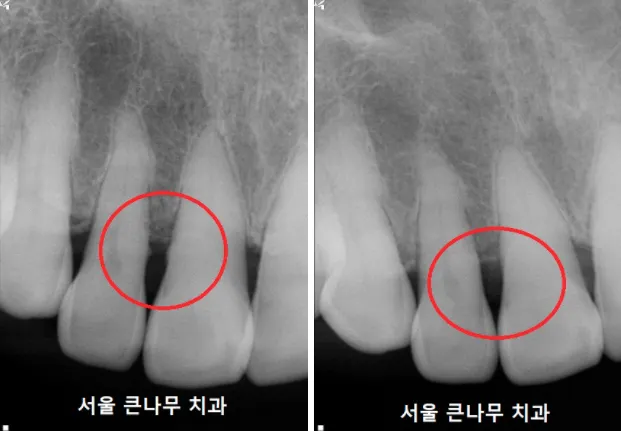

먼저, 치석제거를 진행했습니다. 눈에 보이는 치석은 다 제거하였지만 눈에 보이지 않는 치석은 남아 있었습니다. 사진에 오돌토돌하게 남아있는 치석의 모습을 확인할 수 있었고, 잇몸치료 후 완전히 제거하였습니다.

마찬가지로 치아 뿌리에 자리 잡고 있는 치석을 제거하였습니다. 스케일링만으로는 제거되지 않는 치석입니다.